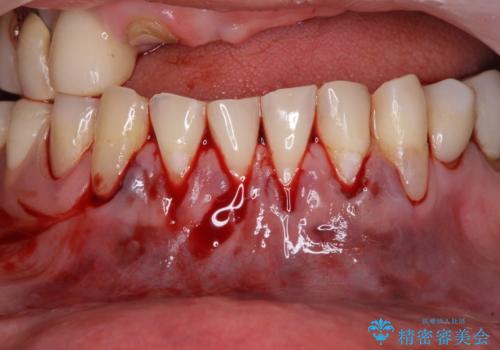

- 咬み合わせにより下の前歯の歯肉が退縮してしまい、根が見えていることが気になるとのことで来院された患者様です。

歯肉退縮に対して、上顎からの結合組織移植術(CTG)により、歯根の被覆を行うとともに、歯肉の厚みを増すことで将来の退縮リスクを抑制することとしました。

歯肉が大変薄かったため、歯肉移植による根面被覆の効果はそれほど高くないように思われましたが、想像以上に歯肉の位置を回復させることができました。